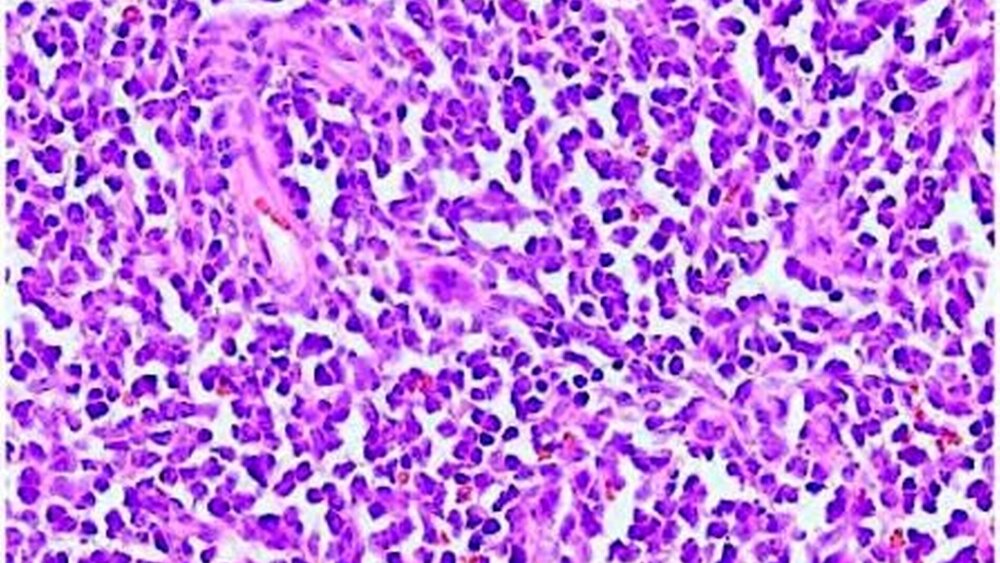

Das bioptisch gewonnene Material (Abbildung 5) imponierte als festes, fast schwartenartiges Gewebe ohne richtungsweisende makroskopische Merkmale. Histologisch (Abbildung 6) zeigte sich eine diffuse Infiltration des Gewebes mit einer monomorphen Zellpopulation blastenartiger Zellen. Unter der weiteren immunhistologischen Diagnostik wurde abschließend die Diagnose einer akuten myeloischen Leukämie gestellt.